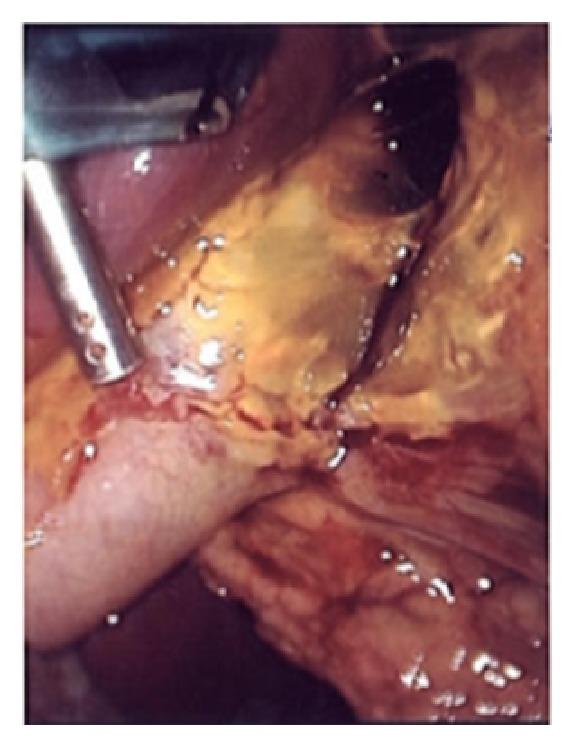

Introduction. Concomitant cholecystitis and gallstone pancreatitis is an infrequent clinical encounter, reported sparsely in the literature. Concurrent acute cholecystitis and pancreatitis complicated by gall bladder perforation has not been reported before. Presentation of Case. We report a 39-year-old female presenting with concomitant cholecystitis and acute pancreatitis, complicated by gallbladder perforation. Discussion. There is much controversy surrounding the timing of cholecystectomy following gallstone pancreatitis, with the recent literature suggesting that "early" operation is safe. In the current case, gallbladder perforation altered the "routine" management of gallstone pancreatitis and posed as a management dilemma. Conclusion. Clinical judgement dictated timing of operative management and ultimately cholecystectomy was performed safely.